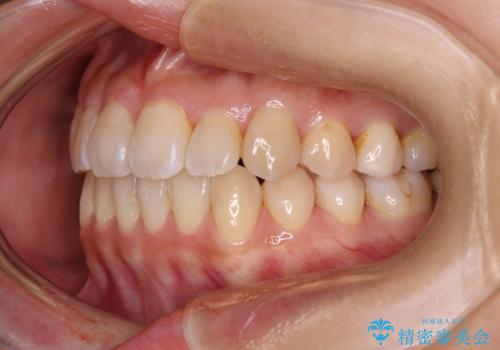

クロスバイトの前歯を改善 ワイヤー装置で楽々矯正治療

- 前歯のクロスバイトを改善したいとのことで来院された患者様です。

マウスピース矯正は自己管理が煩わしいとのことで、ワイヤー装置による矯正治療を行うこととしました。

舌の突出癖が認められたため、デコボコ改善に伴い前歯が前突する可能性があったため、舌のトレーニングをしっかりと行うよう指導しながら治療を進めることとしました。

左下の奥歯は根管治療後に放置されていたため、咬み合わせを調整しながら矯正治療を行い、最後にオールセラミッククラウンにて補綴治療を行うこととしました。